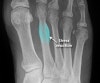

발의 AP view, lateral view, oblique X-ray 촬영을 실시합니다.

손상 후 2~3주까지는 X-ray에 안 보일 수 있으므로 시간이 지나 재촬영을 해야 합니다.

X-ray : 중족골 피로골절(Metatarsal stress fracture)